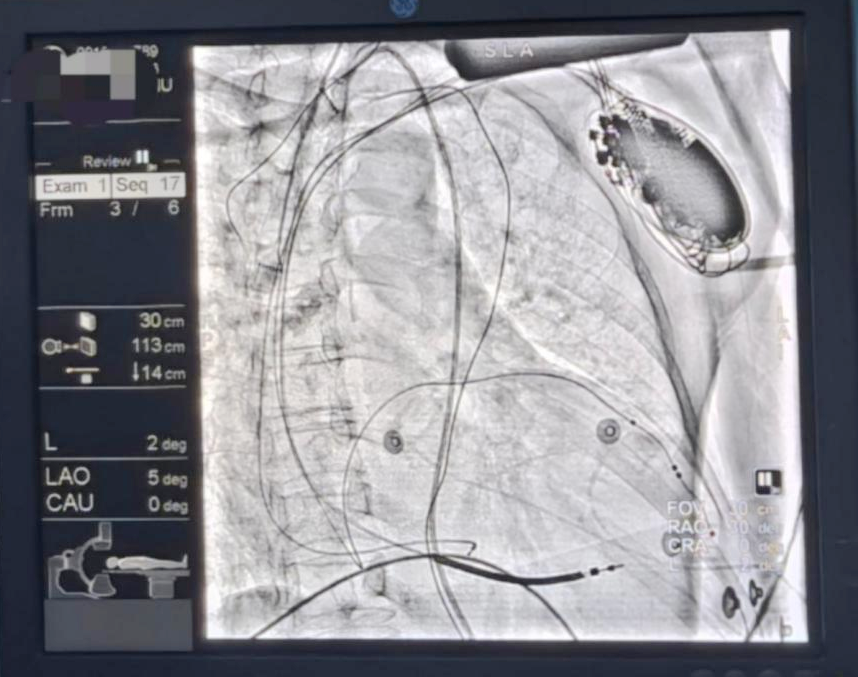

▲术后造影图